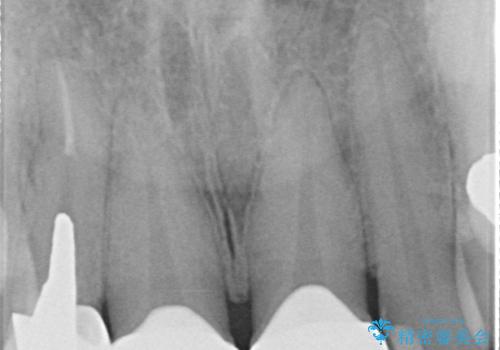

患者様は過去に装着されたラミネートベニアが割れてしまったことに加え、土台との間に隙間が生じており、適合が不良な状態でした。

このままでは見た目だけでなく、むし歯や歯周病のリスクが高まってしまいます。

そのため当院では、上顎左右中切歯を適合精度の高いオールセラミッククラウンにて再補綴する治療をご提案し、実施いたしました。

長期的に歯や歯周組織を守るためには、精密に適合した被せ物を入れることがとても重要です。